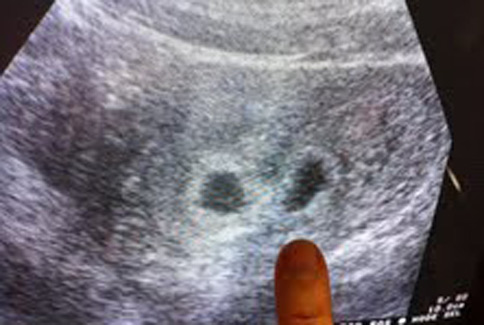

我有多囊卵巢症候群,​在博元婦產科​求子成功懷孕了! 多囊卵巢症候群怎麼治療才會懷孕? 到哪裡治療多囊卵巢症候群? TV177 http://v.youku.com/v_show/id_XNTE0OTU5NjEy.html